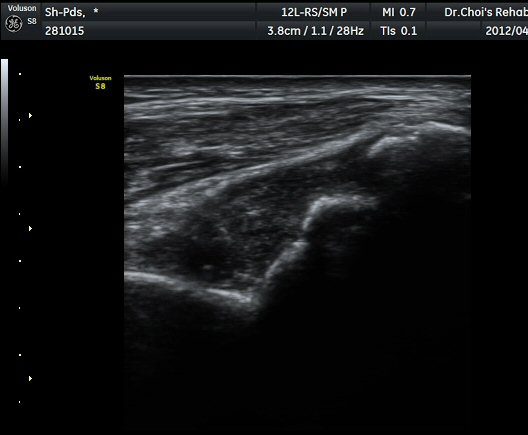

ÃÊÀ½ÆÄ °Ë»ç

ÆÈ²ÞÄ¡°üÀý ¾ÕÀÇ Á¾´Ü¸é°Ë»ç¿Í ÁÖµÎ¿Í Á¾´Ü¸é°Ë»ç¿¡¼­ ½ÉÇÑ °üÀý³» ºÎÁ¾ÀÌ

°üÂûµÊ(»çÁø 1, 2, 3).